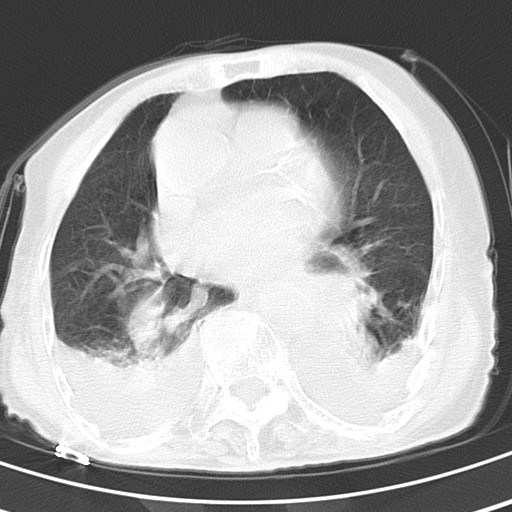

标题: CT21467:女,93岁,摔伤后检查。

女,93岁,摔伤后检查。

考虑感染性病变,建议抗炎治疗后复查。双侧胸腔积液。

右肺炎症,心功能不全伴双侧胸腔积液,右下肺膨胀不全,食管裂孔疝,冠脉钙化,心包少量积液,左侧肋骨骨折,请上传骨窗.

双肺感染合并双侧胸腔积液、胸膜增厚粘连,骨性胸廓未见明确骨折征。

创伤性湿肺,双侧胸腔积液。可能有食管裂孔疝,进一步检查。骨折有无根据自己的机器及片子再仔细看吧。

右肺炎症,心功能不全伴双侧胸腔积液,右下肺膨胀不全,食管裂孔疝,冠脉钙化,心包少量积液,左侧肋骨骨折,右肩甲骨粉碎性骨折。93岁,高寿哇!